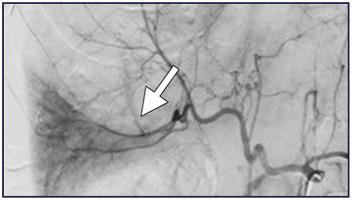

经颈静脉肝活检引起的动脉损伤伴迟发性出血

Arterial Injury from Transjugular Liver Biopsy with Delayed Hemorrhage